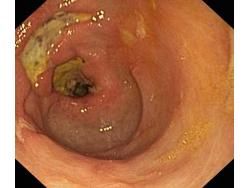

Wrzód trawienny